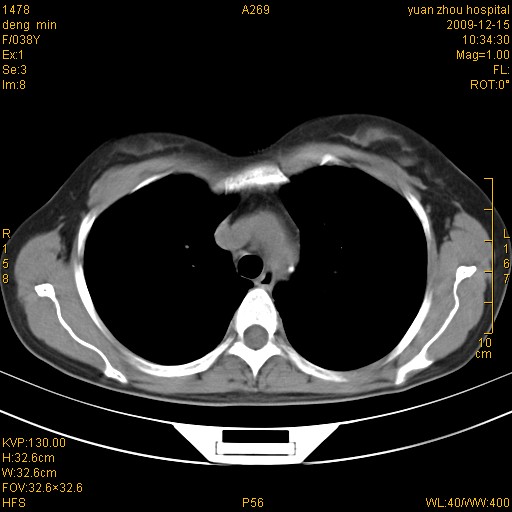

标题: CT23919:F38Y 咳嗽月余 [打印本页]

标题: CT23919:F38Y 咳嗽月余

右肺中下叶、左肺上叶舌段及左肺下叶支气管扩张合并感染。